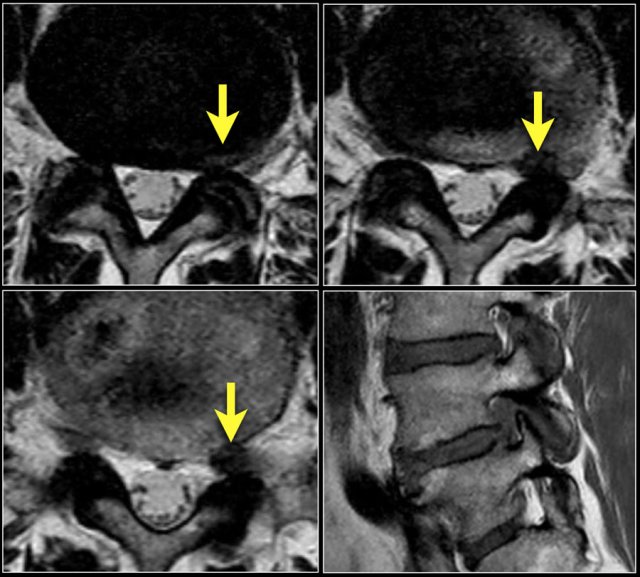

It is better to have continuous slices with the same angulation parallel to the level where nerve compression is suspected.

This has the advantage, that you can follow the involved nerve along the four levels of possible compression.

When you examine multiple levels with different angulation like in the example on the right, you will not be able to follow the whole nerve tract and you will not get the whole picture.